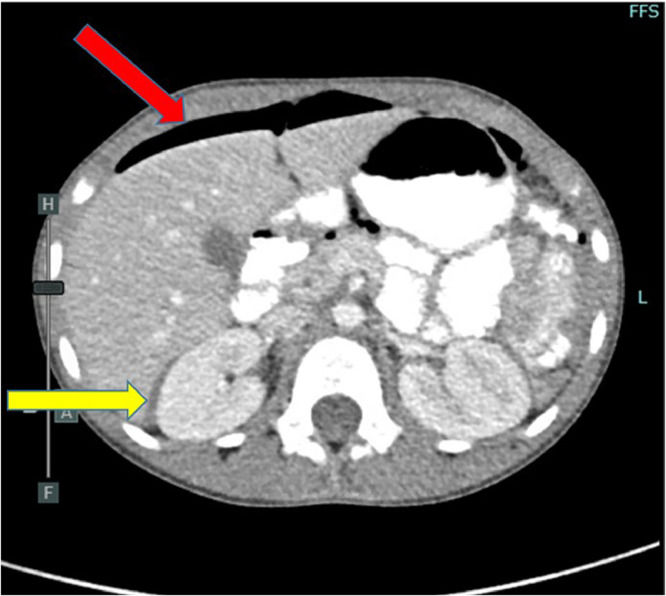

Axial view – CT abdomen/pelvis with IV and PO contrast demonstrating small-volume pneumoperitoneum (red arrow) and complex free fluid in the hepatorenal space (yellow arrow).

Imaging: Small-volume pneumoperitoneum, deemed normal; benign abdominal exam

Imaging: CT abdomen/pelvis showed obscured lower pelvic mass, no contrast extravasation; poor sensitivity due to thin body habitus